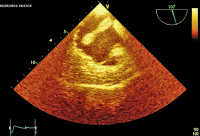

Abbildung 2: Apikaler Vierkammerblick: Lange echoreiche, anscheinlich am Vorhofseptum fixierte Masse prolabiert in die rechte und (weniger sichtbar) in die linke Kammer.